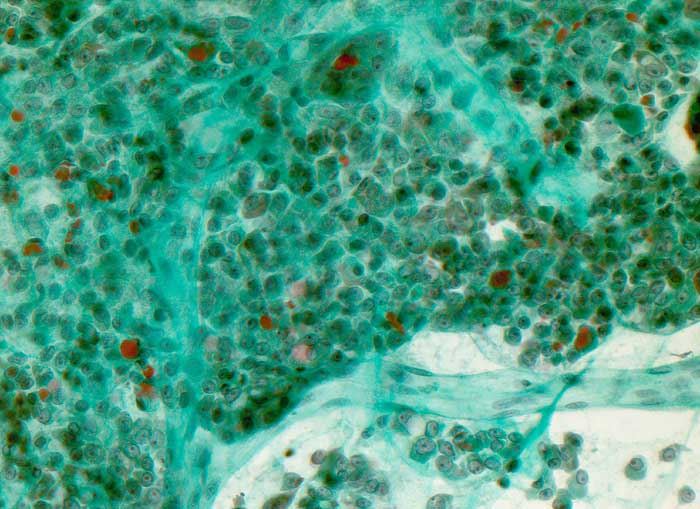

Massenhaft onkozytäre Zellen mit relativ breitem Zytoplasma und unterschiedlich grossen Kernen. Sie enthalten einen besonders auffälligen grossen Nukleolus. Die onkozytären Zellen bilden oftmals kleine mikrofollikuläre Strukturen und sitzen verzweigten fibrovaskulären Achsen auf.

Zytologische Diagnose: Massenhaft Zellen und Zellverbände einer onkozytären Neoplasie mit Kernatypien.

Die Zellatypien, insbesondere die ungewönlich grossen Nukleolen sind suspekt auf ein onkozytäres Karzinom. Eine sichere Unterscheidung zwischen einem onkozytären Karzinom und einem onkozytären Adenom mit Atypien ist aber nicht möglich.